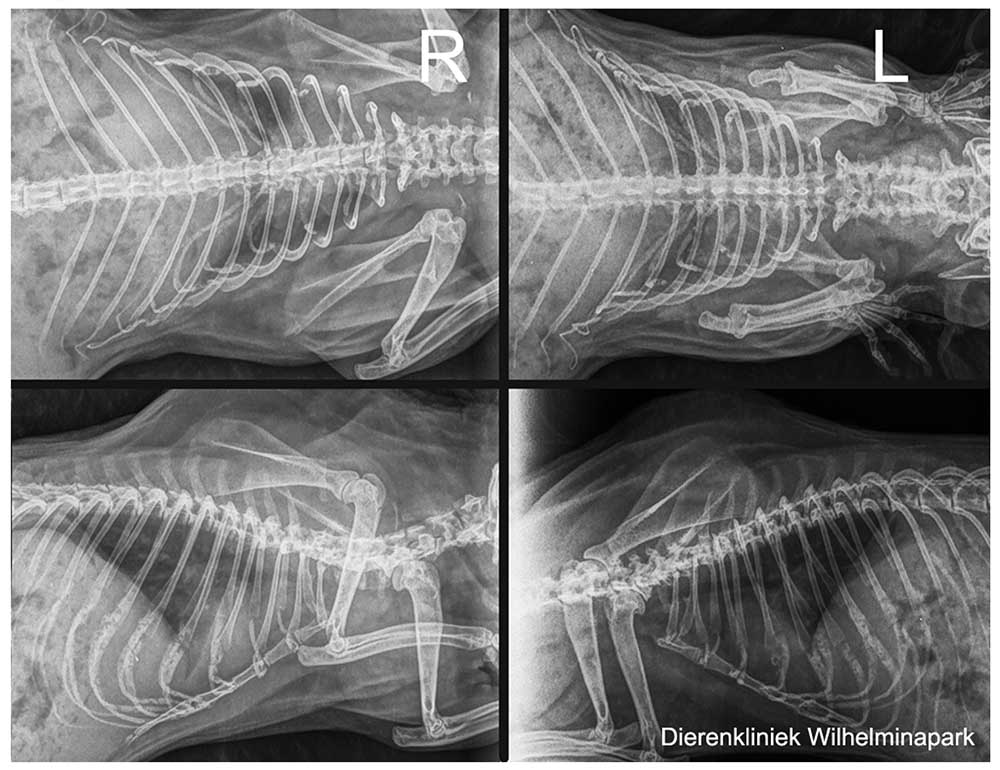

We hebben rontgenfoto's van vier zijden gemaakt. Van links boven naar linksonder met de klok mee: op de rug liggend (VD) en borst buikligging (DV) en twee keer in zijligging - op rechterzijde liggend (SD) en op de linkerzijde liggend (DS) - om een zo goed mogelijk overzicht van de longen en het hart te krijgen.

We hebben de röntgenfoto's laten beoordelen. Zie hieronder: er is een verdenking van een pneumonie (een longontsteking).

Uit het onderzoek kwam een infectie met mycoplasma naar voren.

Beide cavia's zijn goed genezen met de oogzalf en antibioticum, na 2 weken waren de klachten volledig over.

Cavia Tygo was benauwd - er was een zware ademhaling te zien en er was een bijgeluid te horen bij de ademhaling.

Tygo kreeg doxycycline als antibioticum.

De beoordeling van de röntgenfoto: er is een sterke aanwijzing voor een longprobleem. Dan kiezen we voor een ander antibioticum als behandeling.